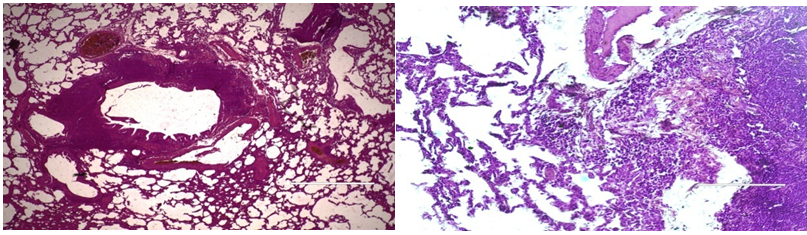

It was found that in the group receiving a dose of staphylococci in the amount of 3 million units, there was a more pronounced development of the pathological process compared to the group of animals administered a dose of 2 million units of staphylococci (Figure 1) (Figure 2). These changes were more significant on the 7th day of the experiment.

Figure1 Lung tissue rats on the 7th day of staphylococcus infection in a dose of 2 million. e Diniz. Inflammatory hyperemia and peribronchial reactive hyperplasia of lymphoid tissue. Uvel. 10x20., Coloration: hematoxylin-eosin.